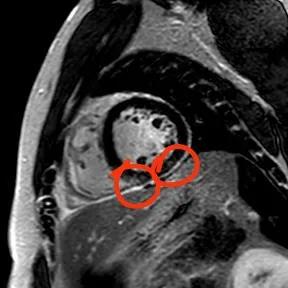

“快!做磁共振觀察心肌有無受損及程度?!庇跋裨\療中心陳寶瑩副主任為小燁進行心臟磁共振平掃及增強掃描。結(jié)果提示:患者有急性心肌損傷,考慮心肌梗死。結(jié)果驗證了小燁的心肌大片區(qū)失活。

方向比努力更重要,對于醫(yī)生而言更是如此,準確把握病因方向,才能有效治療。心臟磁共振,成為非侵入性診斷心肌疾病的金標準,能準確地鑒別心肌炎、應激性心肌病、心肌病淀粉樣變性、擴張性心肌病及心肌梗死等,并能對心肌梗死后心肌纖維化進行定量評估。